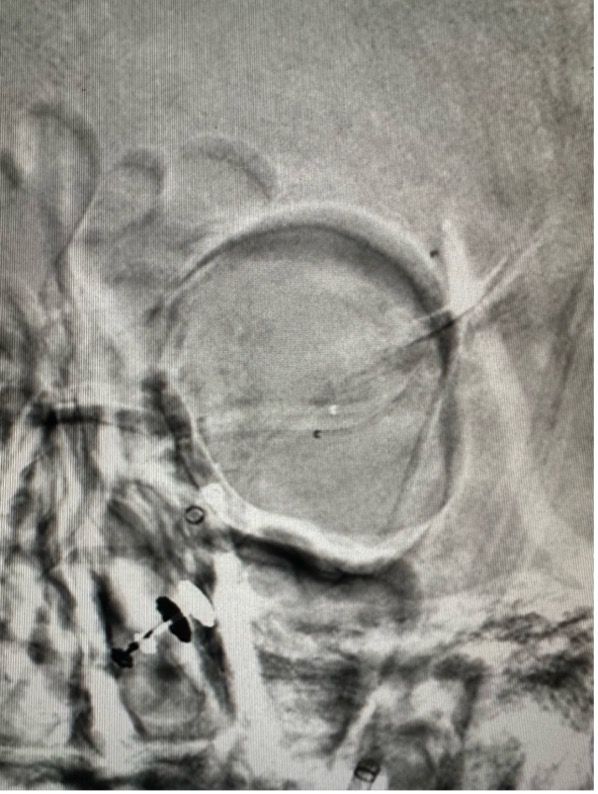

First-in-Human Device Trials

First-ever SEAL aneurysm device trial (8 patients, zero complications, FDA-recognized) and first global enrollment for Gravity Supernova Stentriever system.

Fundraising for the neuroangiography biplane suite at JPMC — the essential machine for performing thrombectomies and treating brain aneurysms.